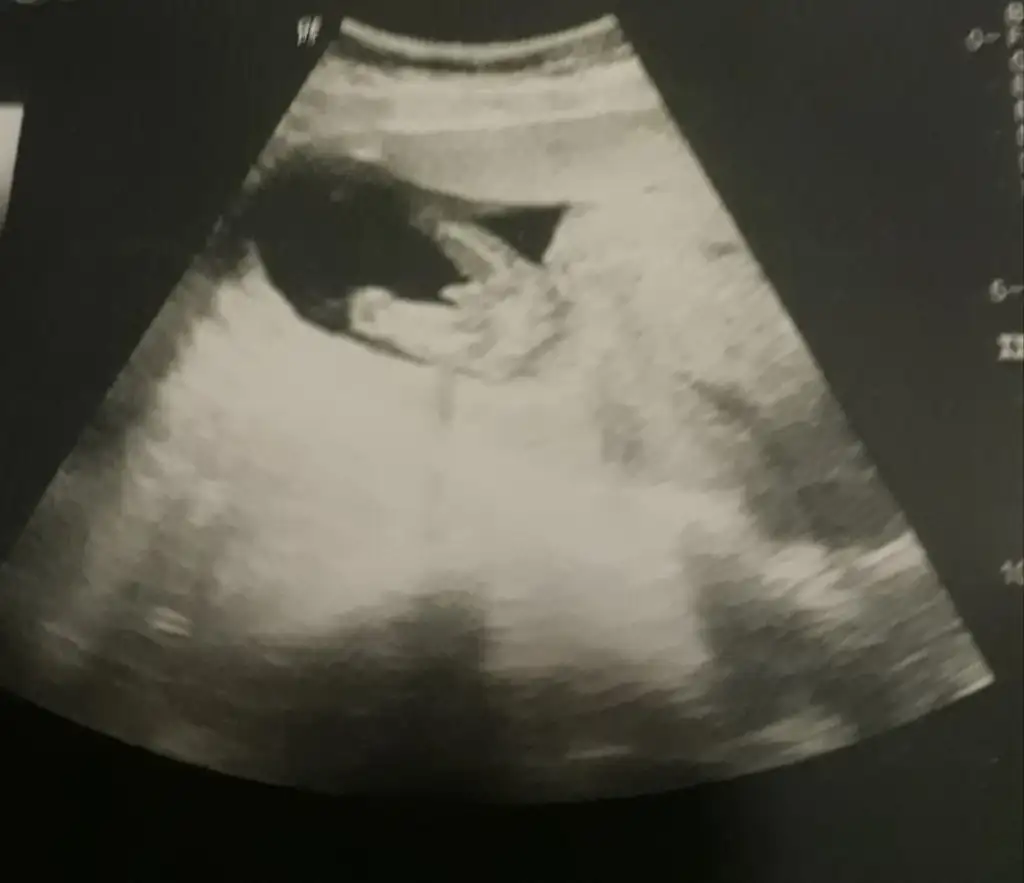

Ben burayı nasıl kaçırmışım.En son ultrason resmimiz 11+3 'ten.Tahmin alabilir miyim arkadaslar🙏

• 20200215_142051.webp

20200215_142051.webp

26,1 KB · Görüntüleme: 65